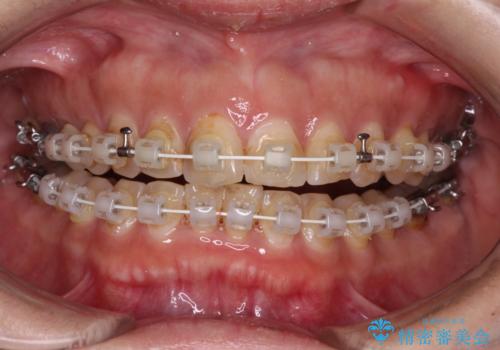

【モニター】飛び出た前歯を整えたい ワイヤー矯正治療

- 飛び出た上の前歯を気にして来院された患者様です。

奥歯の咬み合わせは、上顎歯列が理想的な一よりも数mm前方にある状態でした。

なるべく早めに治療を終えたいとのことで、補助装置を用いて上顎臼歯を後方に移動させ、同時にワイヤー装置にて整えることとしました。

舌の突出癖が原因で上下の歯に大きなスペースが生じていたため、舌のトレーニングをしっかり行っていただくことで、上顎歯列をスムーズに移動させることができました。